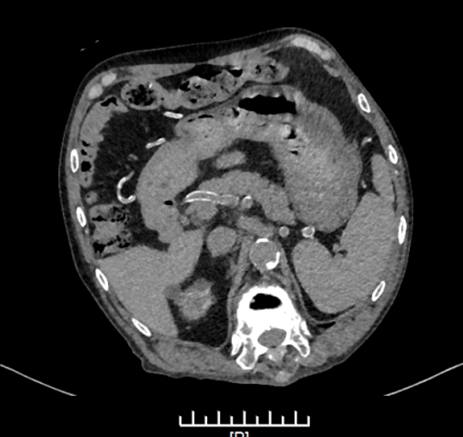

入院后完善相关检查,提示覃老师存在严重骨质病变、血管明显钙化。

CT检查提示胸廓前后径增大

CT检查提示动脉血管壁钙化明显